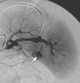

Intrasplenic hematoma